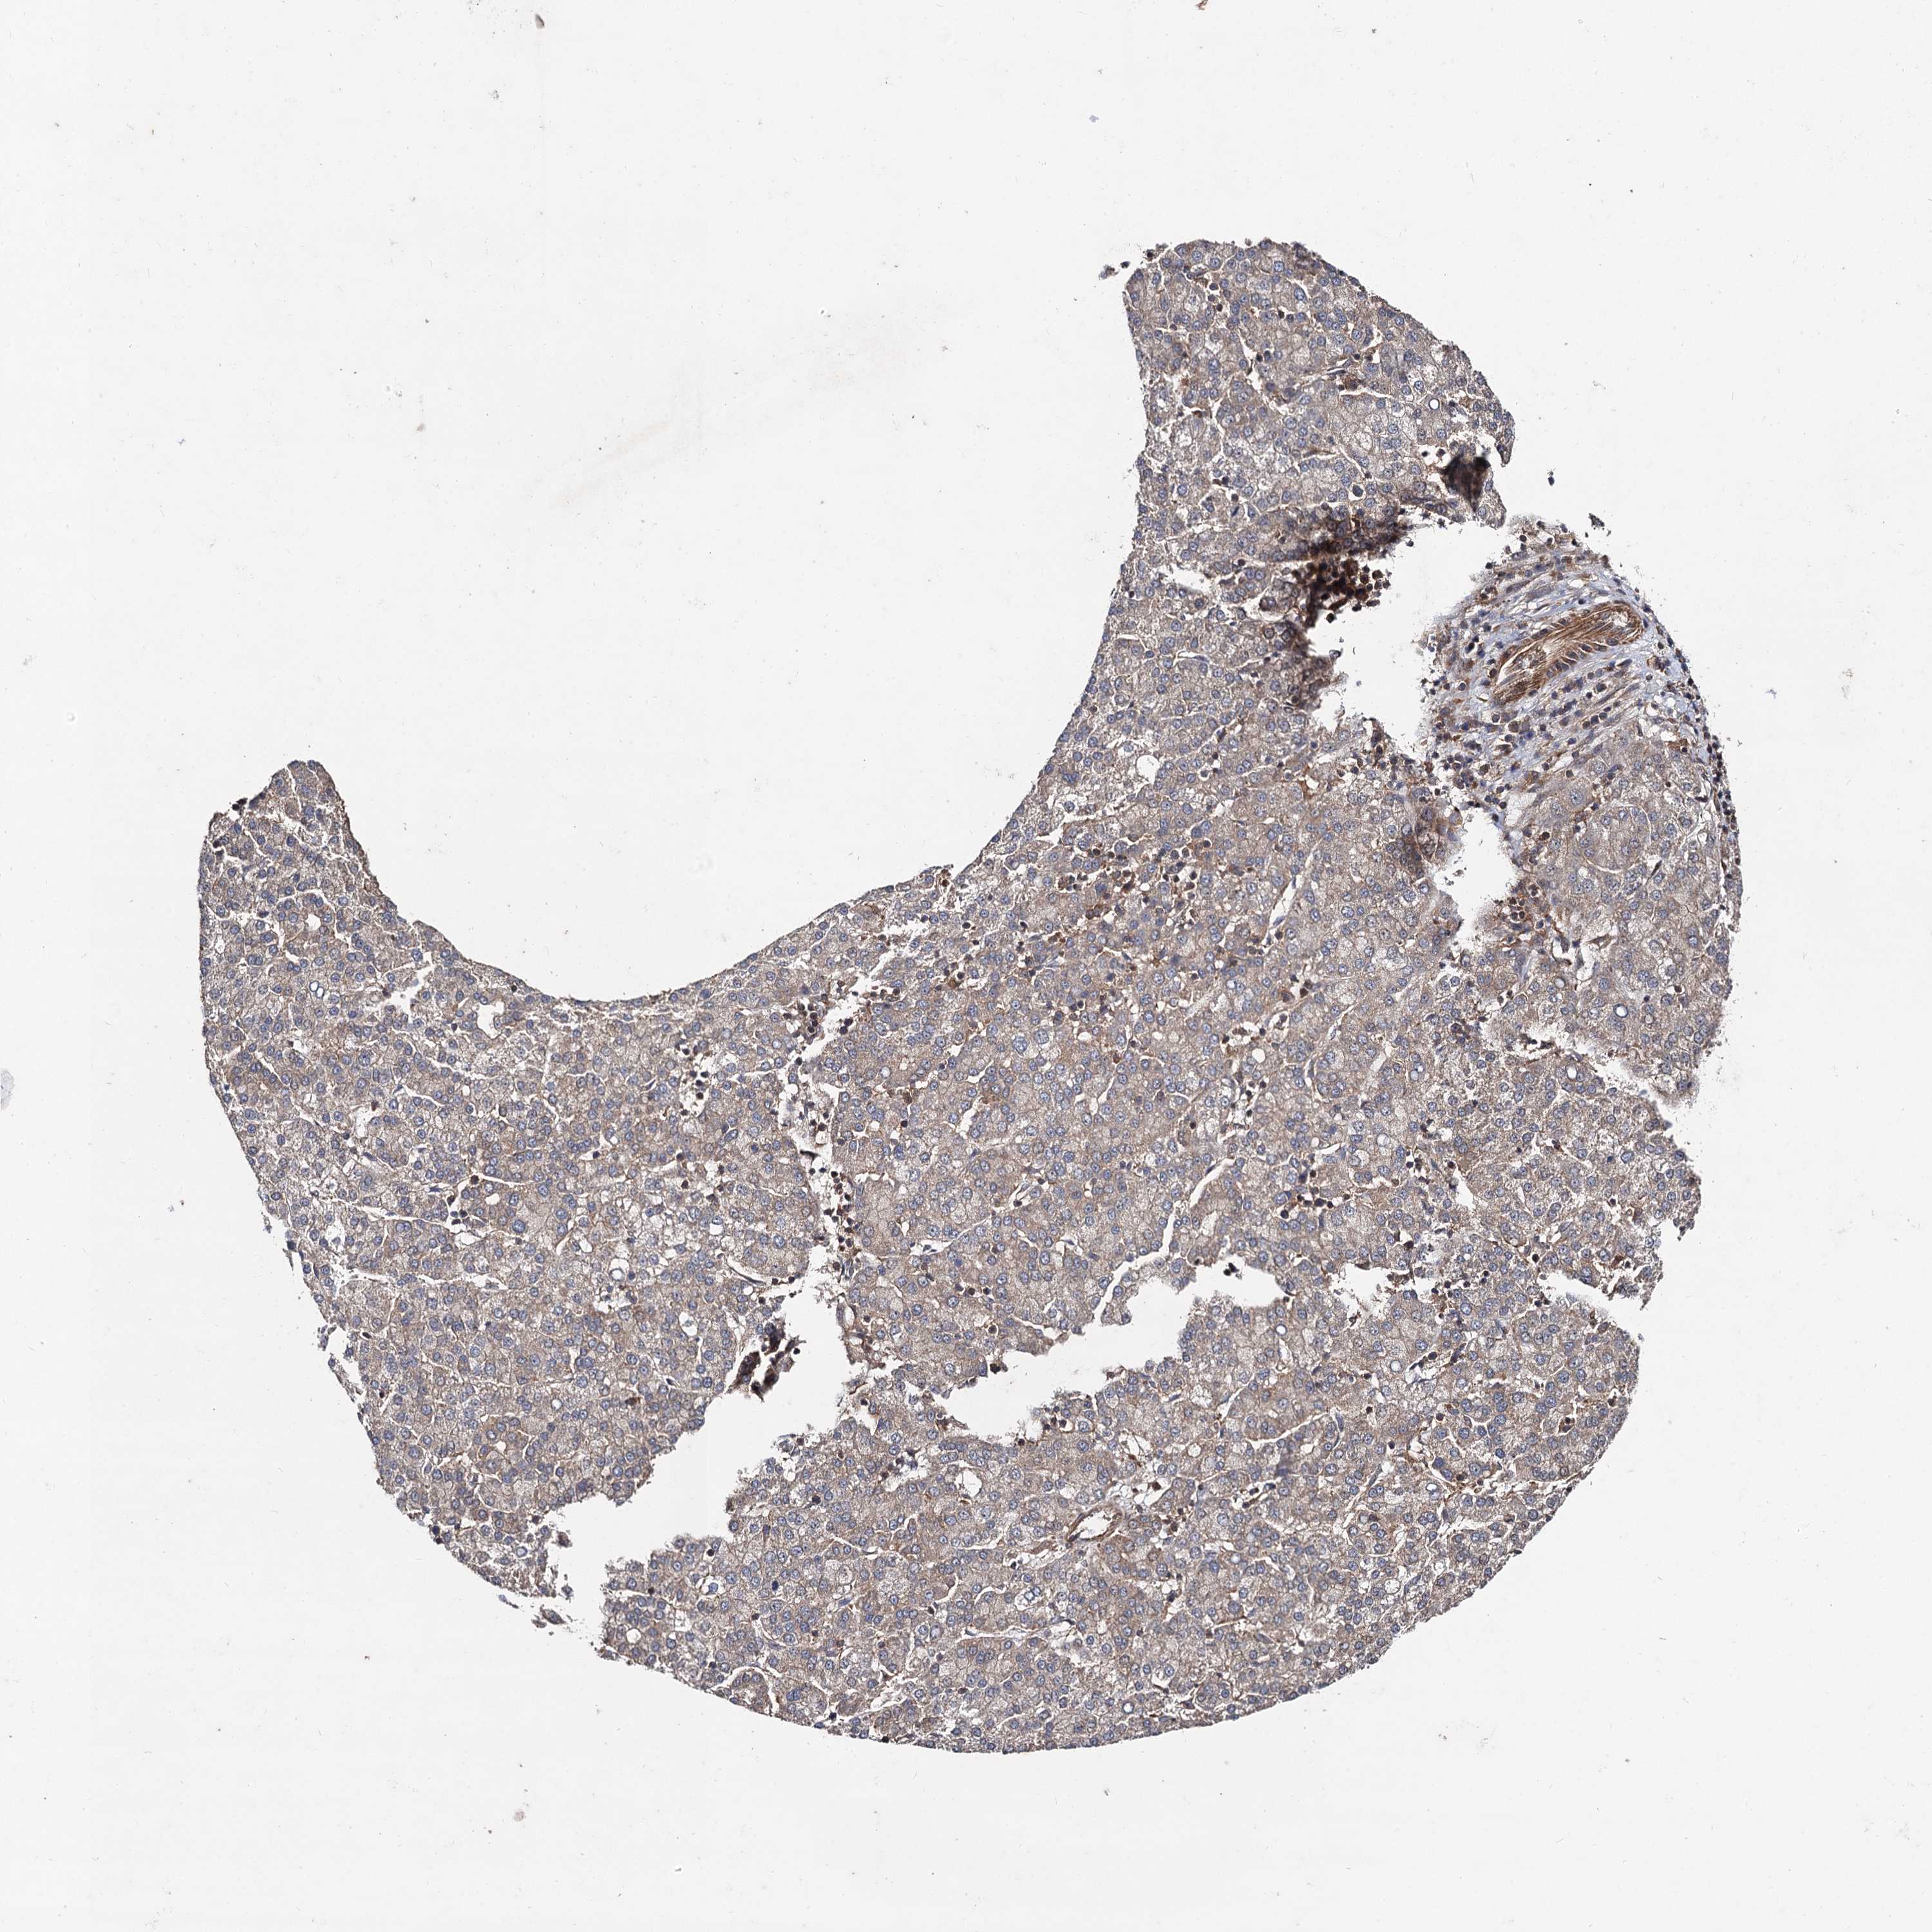

LIVER CANCER - Protein expressioni

A mouse-over function shows sample information and annotation data. Click on an image to view it in a full screen mode. Samples can be filtered based on level of antibody staining by selecting one or several of the following categories: high, medium, low and not detected. The assay and annotation is described here.

Note that samples used for immunohistochemistry by the Human Protein Atlas do not correspond to samples in the TCGA dataset.

Antibody stainingi

Antibody staining in the annotated cell types in the current human tissue is reported as not detected, low, medium, or high, based on conventional immunohistochemistry profiling in selected tissues. This score is based on the combination of the staining intensity and fraction of stained cells.

Each image is clickable and will lead to virtual microscopy that enables deeper exploration of all samples and also displays staining intensity scores, fraction scores and subcellular localization as well as patient and tissue information for each sample.

Antibody HPA041507

Antibody HPA041599

Cholangiocarcinoma

Carcinoma, Hepatocellular, NOS